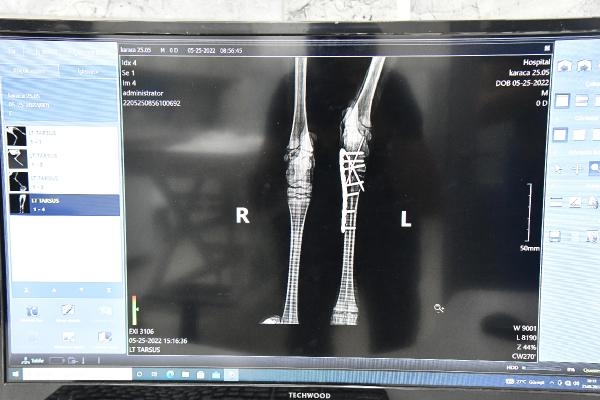

Balıkesir Büyükşehir Belediyesi Çevre Koruma ve Kontrol Dairesi Başkanlığı'na bağlı Ovaköy Sokak Hayvanları Bakımevi'nde görevli veteriner hekimler, evcil hayvanların yanı sıra doğal ortamda yaralanan hayvanların tedavi ve bakımlarını da gerçekleştiriyor. Son olarak Doğa Koruma ve Milli Parklar Balıkesir Şube Müdürlüğü tarafından yaralı olarak bulunan yavru karaca, Ovaköy Sokak Hayvanları Bakımevi'ne getirilerek tedavi altına alındı. Ayakta durmakta zorlanan karacanın sol arka ayağına röntgen çeken Veteriner Hekim Serhat Meşe, ayağının kırık olduğunu tespit etti. Veteriner Meşe, karacayı sağlığına kavuşturmak için ameliyata aldı. Ameliyatın başarılı bir şekilde tamamlanmasının ardından karaca yeniden ayağa kalktı.

Başarılı bir operasyon gerçekleştirdiklerini belirten Veteriner Hekim Serhat Meşe, "Karacanın sol arka ayağında (tarsometatarsal) eklemde kırık tespit edilmesinin ardından plaka uygulayarak stabilize ettik. Şu anda karacamızın neşesi yerinde. Ciddi bir ameliyat atlattı, biraz ağrıları olacak. Ayağına plaka uygulaması yaptığımız için bir ay boyunca Ovaköy Sokak Hayvanları Bakımevi'nde bizim gözetimimiz altında kalacak. Karacamız genç olduğu için hızlı bir şekilde toparlayacaktır. Merkezimizde hastalıkların tespit edilmesi ve tedavi sürecinin sorunsuz bir şekilde yapılabilmesi için tüm araç gereçlerimiz mevcut. Bu sayede merkezimize gelen hayvanlarımıza sadece iyileşmek için çaba göstermeleri gerekiyor. Merkezimizin tam donanımlı olarak hizmet verebilmesi için hiç şeyden kaçınmayan Başkanımız Yücel Yılmaz'a çok teşekkür ediyorum" dedi.